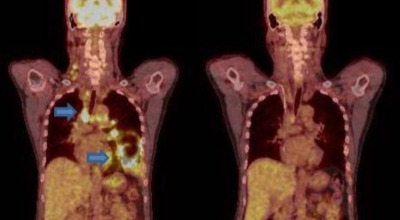

폐암 검사는 주로 X-ray를 통해 이루어지지만, 종양의 크기가 작거나 구석에 위치한 경우에는 확인이 어려운 경우도 있습니다. 그 후, 조직 검사를 통해 정확한 진단을 하게 됩니다. 폐암이 발견되면, 종양의 크기, 전이 여부, 위치에 따라 수술 여부를 결정하게 됩니다.

수술 치료

악성 종양이 있는 폐의 일부를 절제하는 방법으로, 초기 단계에서는 내시경 기구를 활용하여 수술이 가능하기도 합니다.

항암 치료

항암제를 이용한 치료 방법으로, 특히 폐암 4기와 같은 경우에는 항암 화학요법이 유일한 치료 방법일 수 있습니다.